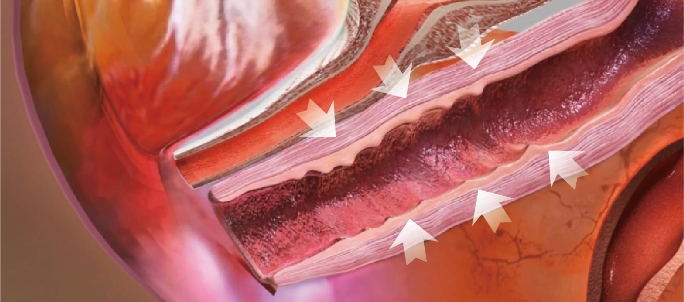

Thermal stimulation of entire vaginal wall layer

Immediately after treatment, shrinkage of the vaginal skin fibers occurs. In addition, collagen growth is promoted and the vaginal wall becomes resilient and thick. Changed Vaginal structure after treatments makes its whole conditions better.

Before

After

Effect of Laser Treatment Collagen Stimulation

- Vaginal Remodeling

- Vaginal Dryness

- Sexual Dissatisfaction

- Pelvic Organ Prolapse

- Urinary Incontinence

Before the treatment Loosen vagina inner wall